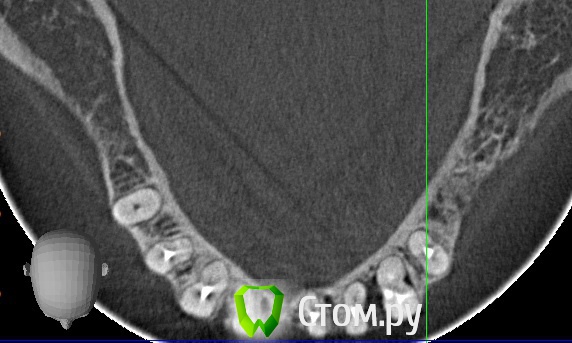

stradalitca Опубликовано 29 мая, 2014 Автор Поделиться Опубликовано 29 мая, 2014 Всем добрый вечер! у меня есть новая информация по поводу перфорированной тройки снизу слева. я ещё раз досканально просмотрела. Оказывается она пробита не ровно между отростками корня, там всё цело. а пробит по сути один отросток корня. Может ещё не поздно закрыть чем-либо эту перфорацию? что скажете( штифт поставили примерно 15-20 декабря)? Ссылка на комментарий

Korel Опубликовано 6 июня, 2014 Поделиться Опубликовано 6 июня, 2014 всем добрый вечер! А если рассматривать бюгельный протез, то надо будет вовлекать правую восьмёрку и одевать на ней коронку?я совсем запуталась... Не на одном срезе не нашёл апекс 48 , надо сначала посмотреть его, затем снять мост, оценить коронкОвую часть, подвижность и проч. Если всё Ок, то запараллелить, закрыть литьём и кмк можно использовать. Конечно надо смотреть очно. Ссылка на комментарий